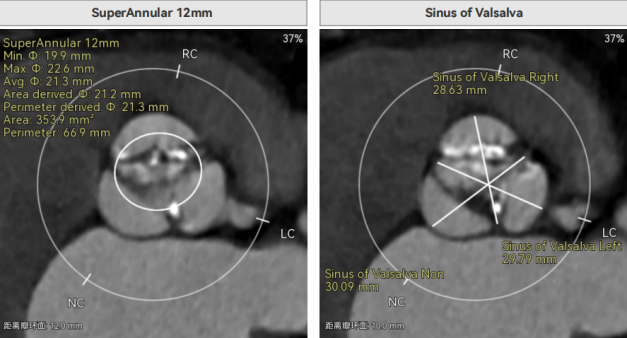

许金鹏教授 安徽省胸科医院 干瓣耐久首选之,15年承诺佑病患:随着病患的复杂性提高及TAVR二次手术窗口期的慢慢到来,摆在临床面前的是如何提升瓣膜使用的耐久性?预装干瓣的获批上市无疑为临床提供了全新的选择。预装干瓣摆脱了传统戊二醛保存的束缚,通过专利抗钙化技术及干式保存工艺打造了一款兼具“曲柔性”和“不沾钙”瓣叶的介入瓣,预期会有更耐久的使用寿命。此次病例患者小瓣环,Prostyle A®自膨瓣的收腰设计,为冠脉开口预留了“生命通道”,而平衡的收腰设计又很好的保证了开口面积,为小瓣环患者血流动力学提供的牢靠的保障。 期待这样一款基于临床需求的性能平衡的耐久干瓣,护佑 TAVR广大患者的全生命周期管理! 患者病史 主要诊断:非风湿性主动脉瓣狭窄(重度);非风湿性主动脉瓣关闭不全(中度);非风湿性二尖瓣关闭不全(中度);心脏扩大(左房明显扩大、左室略大);肺动脉高压(估测肺动脉收缩压约 39mmHg);胸椎压缩性骨折(T9 椎体,考虑新鲜);肺部阴影(两肺慢支改变、多发结节);胆囊术后; 入院检查:BP 109/60mmHg、心率 77 次 / 分(律齐),神清精神可,口唇不绀。 术前超声提示 主动脉瓣钙化并狭窄(重度)伴反流(中量),Vmax509cm/s,PGmax105mmHg;升主动脉增宽;左房明显增大,左室略大;二尖瓣关闭不全伴反流(中+量);瓣尖轻微增厚;室间隔增厚; 术前CT 三叶瓣(L-N融合,功能型二叶瓣),瓣叶增厚中度钙化,钙化主要分布在左冠窦瓣叶边缘及左无融合处、右冠瓣叶基底及边缘,主动脉瓣环径22.2mm,LVOT21.1mm,呈略直通型;双侧冠脉开口高度可,窦部空间大,VTC距离够,预估冠脉低风险,STJ、升主动脉内径可;左室内径可,主动脉水平夹角47°,非横位心。主动脉弓角弓距可;外周入路无明显迂曲,无钙化,两侧股动脉内径可,均可通过20F大鞘,右股低分叉。 手术策略 推荐右侧股动脉为主入路,左侧股动脉为辅助入路,使用20F大鞘,右股分叉上方1cm穿刺。推荐选择AV23瓣膜,18mm球囊预扩,最终理想位置瓣下2mm。 手术过程 在右股动脉穿刺建立通路后,顺利送入大鞘,经食道超声及血管造影确认路径稳定。18mm球囊预扩后评估冠脉灌注良好,后将Prostyle A® AV23瓣膜精准释放于目标位置,超声显示无瓣周漏,术后即刻造影显示无明显反流,导管测平均跨瓣压差8mmHg,心功能明显改善,患者生命体征平稳。 主动脉根部造影 18号球囊预扩 输送器顺利过弓 迅速锚定,平稳释放至工作位 最终造影,位置形态良好,无瓣周漏 Prostyle A®预装干瓣——助力临床最优化解决方案 预装干瓣 便捷顺安:金仕生物专利抗钙化技术运用纳米技术去除组织内的细胞碎片和磷脂,封闭游离醛基,从根本上阻断了瓣膜钙化的多项因素,显著提升了瓣膜的耐久性;同时,相比较传统戊二醛保存方式,干式存储最大限度的保留心包的亲水亲油平衡,还原组织天然曲柔性,进一步保障了瓣叶开合,保证长期耐久性; 流入端桶状设计:流入端桶状的设计,迅速稳定锚定,减少手术时间的同时进一步保障了术中安全; 平衡的收腰设计:该病例左冠高度10.8mm,AV23瓣膜的平衡收腰设计既确保了冠脉开口安全性,又保证了EOA,有效降低了循环崩溃风险,而术后8mmHg的压差的表现更加证明了优秀的血流动力学,进一步提高了瓣膜的耐久性。 专家简介 许金鹏 安徽省胸科医院(点击查看专家详细简历) · END ·